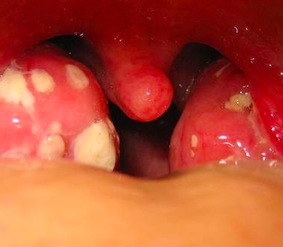

• rigonfiamento e irritazione delle tonsille

Solitamente per giungere alla diagnosi di mononucleosi basta il riconoscimento di segni distintivi tra cui la presenza di placche bianco-giallastre sulle tonsille e il rigonfiamento a livello di milza e fegato.